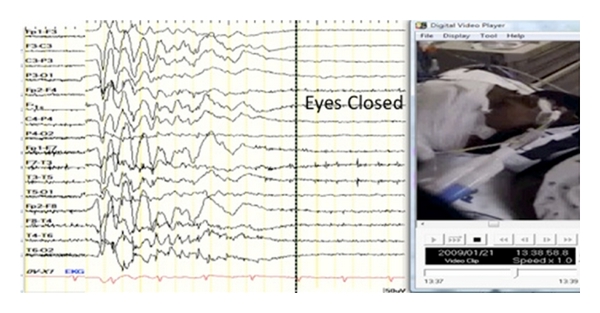

A 12-year-old previously healthy boy was found in cardiopulmonary arrest following prolonged smoke inhalation. Neurologic examination revealed a comatose child with minimally reactive pupils, flaccid tone, and diffuse areflexia. Post-resuscitation he was placed on continuous electroencephalographic monitoring where he was observed to have periodic eyelid opening occurring at 20-second intervals in the absence of other movements. The eyelid opening did not coincide with onset of generalized bursts (Figure 1), as has been reported in similar patients [1–5]. Following intravenous anticonvulsant therapy, eyelid opening did not cease, the electroencephalogram eventually became isoelectric, and the patient died within 48 hours of initial insult.

Video demonstrates a continuous recording of a burst suppression electroencephalogram associated with periodic movements of eyelid opening. As demonstrated in the video, eyelid opening occurred at the near conclusion of the epileptiform bursts and was not suppressible with anticonvulsant therapy.